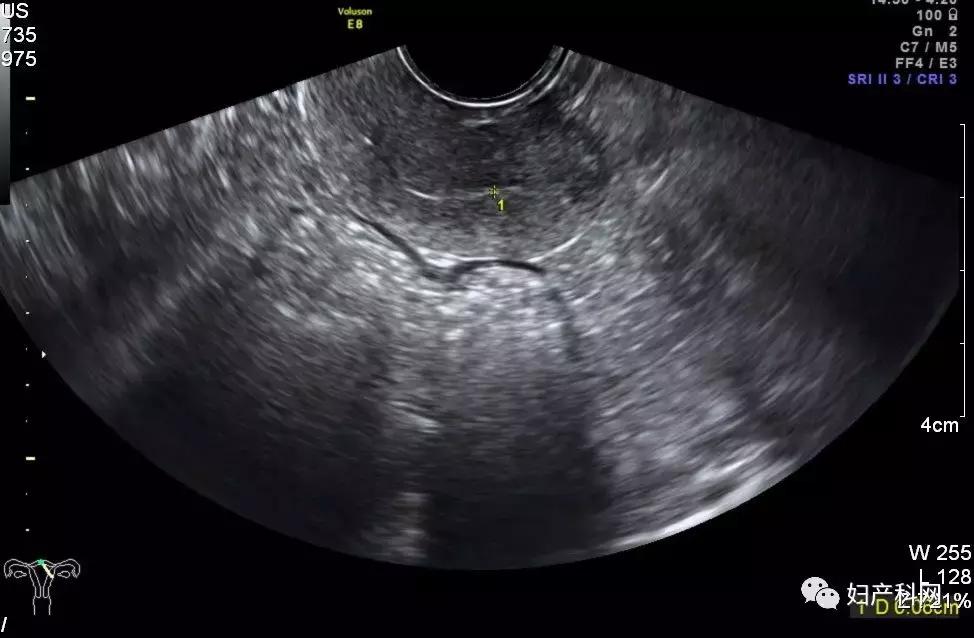

B超(图像如下):子宫后位,萎缩,内膜厚0.12 cm(单层),宫腔内见2.4*2.0*1.5 cm偏强回声,内见星点状血流,子宫右后壁见1.6*1.5*1.2 cm低回声,见包膜血流,双卵巢可及,萎缩。诊断结果:子宫肌瘤,宫腔内偏强回声,建议进一步检查。

2019.2.18盆腔B超(图像如下):子宫后位,萎缩,内膜厚0.1cm(双层),于子宫右后壁见1.4*1.4*1.0cm低回声,边界清,双卵巢可及,萎缩。诊断结果:子宫萎缩,子宫肌瘤。